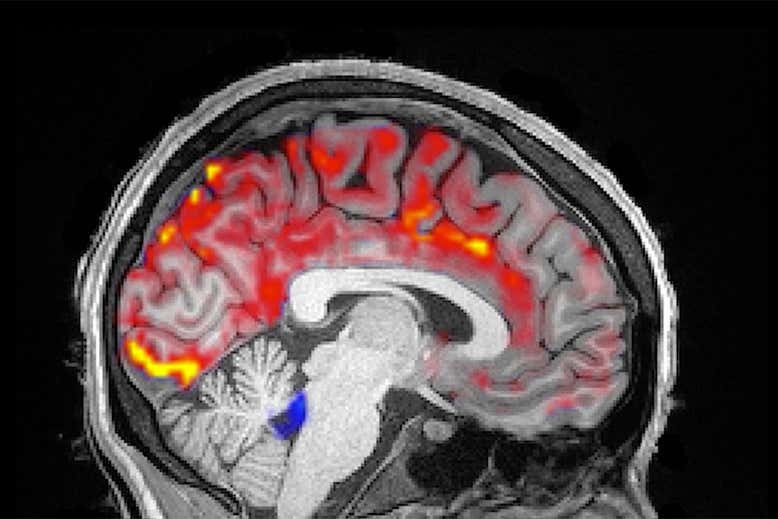

Oxy máu trong não (màu đỏ) khi ngủ.

Các sóng não được tạo ra bởi một mạng lưới lớn của các tế bào não phóng ra cùng nhau theo nhịp điệu. Phần lớn chức năng của nó là không rõ ràng, nhưng chúng ta biết chúng trở nên chậm hơn khi ngủ sâu và nhanh hơn khi chúng ta thức giấc. Để biết rõ vai trò của các sóng não trong vai trò làm sạch bộ não, Lewis và nhóm nghiên cứu của cô đã sử dụng điện não đồ để đo lường hoạt động điện não của 13 người trong khi họ chợp mắt bên trong máy quét MRI.

Cùng lúc, các nhà nghiên cứu cũng đo lường lượng oxy máu trong não bộ và dòng chảy của dịch não tủy, một chất nước lỏng xung quanh bộ não và tủy sống.